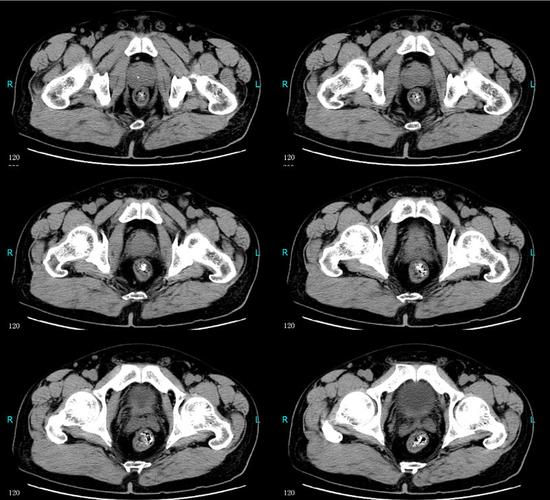

膀胱癌(低级别非浸润性尿路上皮癌)

患者ct结果—箭头处为膀胱肿瘤